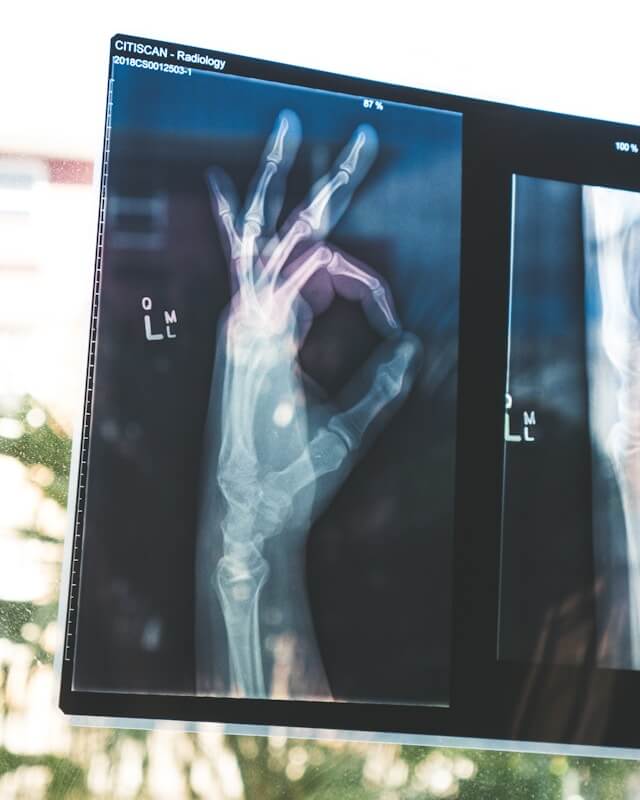

- 골절

골다공증의 가장 흔한 증상 중 하나로, 가벼운 충격이나 낙상으로도 쉽게 골절이 발생할 수 있습니다. 특히 손목, 척추, 엉덩이 골절이 흔합니다. - 통증